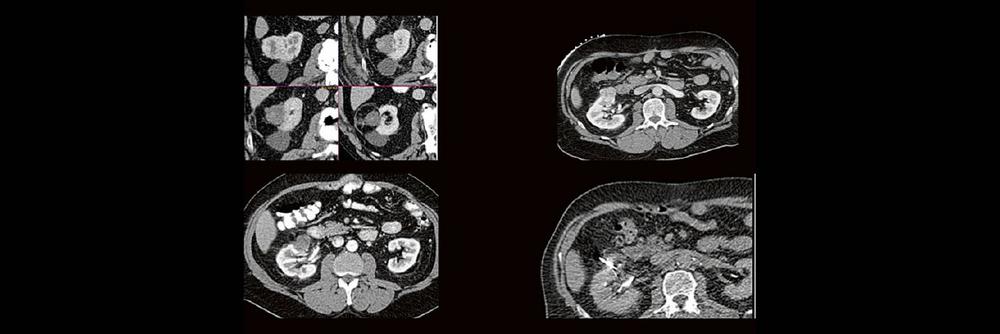

Dr. med. Sascha Alexander Pietruschka Die Anwendung von ablativen Verfahren hat sich in der klinischen Praxis etabliert. Nierentumoren bieten sich für den Einsatz von RFA und Mikrowelle an. Im Dietrich Bonhoeffer Klinikum Neubrandenburg blicken wir auf 15 Jahre Erfahrung mit mehr als 100 RFA/Mikrowellenablationen von Nierentumoren zurück. Im Vortrag werden die eigenen Erfahrungen und Ergebnisse